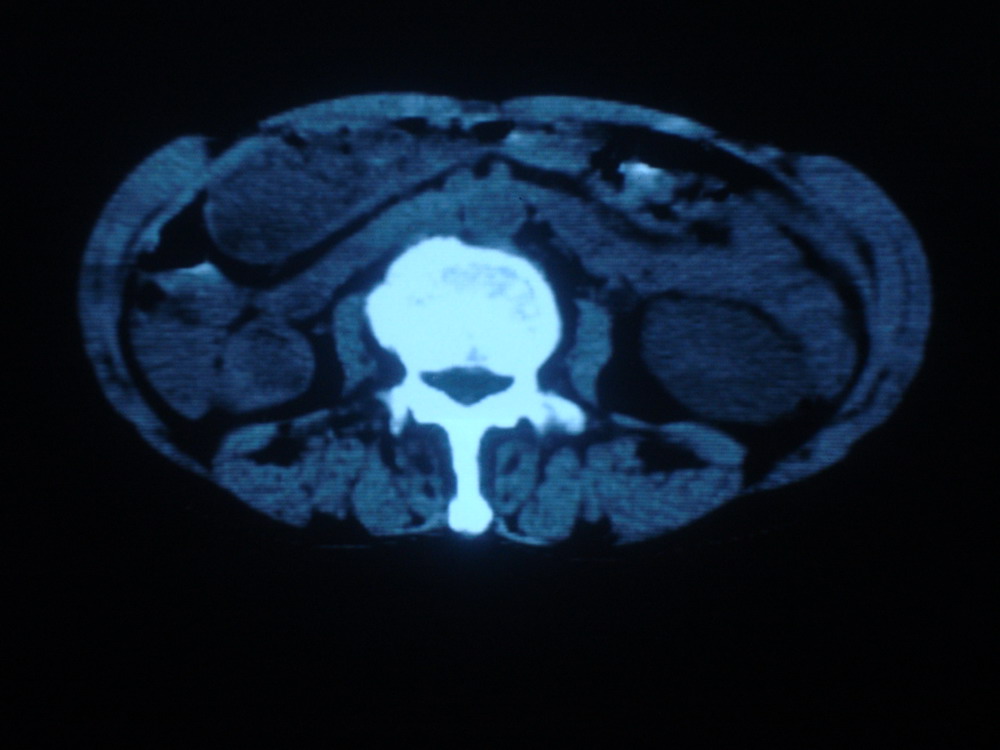

以下是引用卜一在2009-4-1 19:39:00的发言:[br]右肾发育不全、结石、积水并感染可能;左肾结石,代偿性增大。支持!

以下是引用随缘的人在2009-4-1 20:42:00的发言:[br]右肾发育不全、结石、积水并感染可能;左肾结石,代偿性增大。支持!